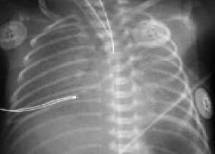

Снижение пневматизации легких, воздушные бронхограммы, границы сердца на рентгенограмме ещё различимы (Рис.5).

Рисунок 5. РДС. Рентгенограмма в прямой проекции, в горизонтальном положении. Верхние доли легких и средняя доля справа неоднородно слабоинтенсивно затемнены, корни легких расширены, не структурны. Сосудисто-интерстициальный рисунок легких деформирован, усилен, размыт. Тень средостения с нечётким контуром, протекционно смещена влево за счёт подворота. ( Диагностика и лечение РДС недоношенных // метод. рекомендация, 2007)